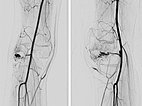

Nach erfolgreicher Embolisation der beiden AVM-Nidusanteile zeigt sich in den Röntgenübersichtsbildern (links a.-p., rechts seitliche Projektion) ein vollständiger Ausguss der beiden Anteile durch das Embolisat, der sogenannte Cast. Dieser besteht aus Ethylen-Vinyl-Alkohol-Kopolymer.

In der Kontroll-DSA (links a.-p., rechts seitlich) nach Embolisation mit Ethylen-Vinyl-Alkohol-Kopolymer zeigt sich auch in einer langen Serie keinerlei Perfusion mehr in der Angiographie. Die AVM gilt als verschlossen.